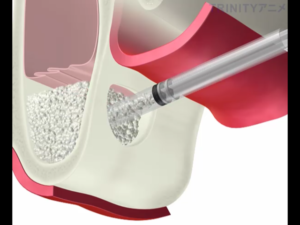

『サイナスリフトとは?』

下の図のように上顎の骨が少なく、副鼻腔との距離が近く骨を盛り上げる場合に選択する治療方法です。

歯茎を切開し、副鼻腔につながる骨を一部削除します。

副鼻腔内の粘膜を破らないように慎重に上方に持ち上げていきます。

それによってできた副鼻腔内の空洞に人工骨を填入します。

骨を盛り上げた部分にインプラントを埋入します。